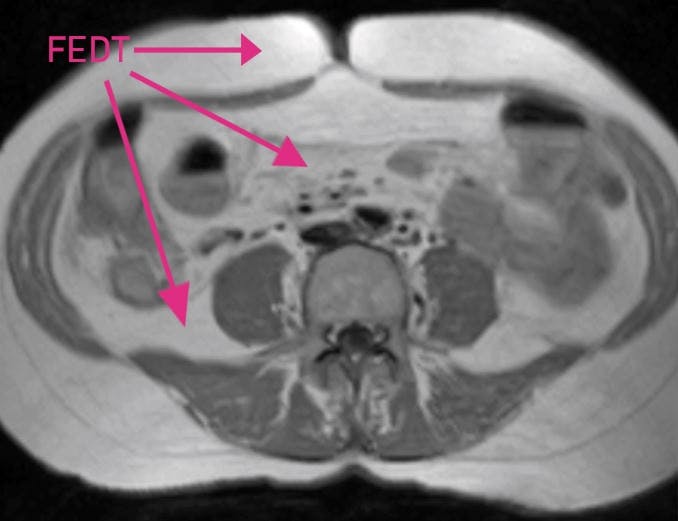

MAVEFEDT LIGE UNDER HUDEN Tværsnit af mave. Personen her har en del mavefedt (det hvide) lige under huden, men har minimalt med fedt mellem indvoldene.